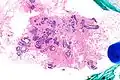

| Very low magnification micrograph of atypical ductal hyperplasia (ADH). The piece with ADH was circled by the pathologist with a marker, as it is so small, and sent for an additional opinion. H&E stain. | |